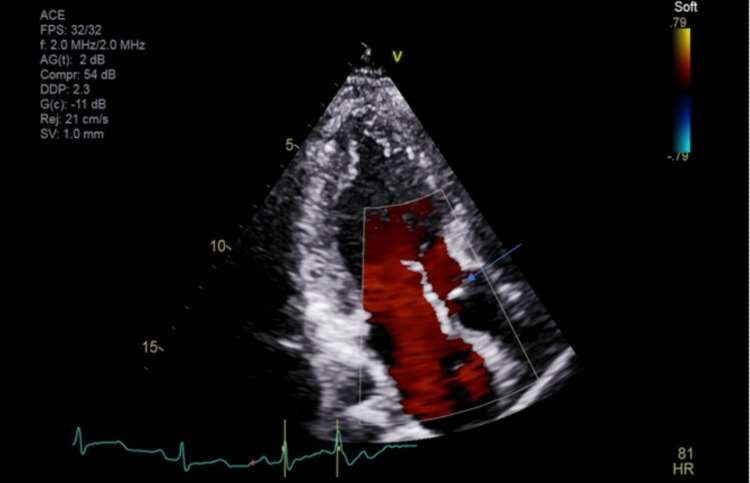

A cardiologist was consulted post echocardiography (Figures 2, 3). There was concern of cardiac arrest caused by ventricular tachycardia induced by prolonged QT interval and multiple PVCs. Unclear if long QTc was an acquired or congenital abnormality. She was transferred to a tertiary center for further workup. In the tertiary center coronary artery CT angiogram showed a calcium score of 0, pseudoaneurysm of membranous septum measuring 12mm x 7mm without any coronary anomalies which is a new finding from the CT angiogram. Cardiac MRI showed no infiltrative process, EF 52%, Qp: Qs 1.5, and subtle mid-wall enhancement of the basal septum. Electroencephalogram (EEG) was performed and possible seizure activity was ruled out. Electrophysiology study was significant for inducible PVCs localized to the free wall right ventricular outflow tract (RVOT), ablated successfully. The team implanted an implantable cardioverter-defibrillator (ICD). A repeat electrocardiogram (EKG) was performed (Figure 4). She was discharged with nadolol 40mg daily and advised against the usage of marijuana. Long QT syndrome genetic panel sent and result pending.